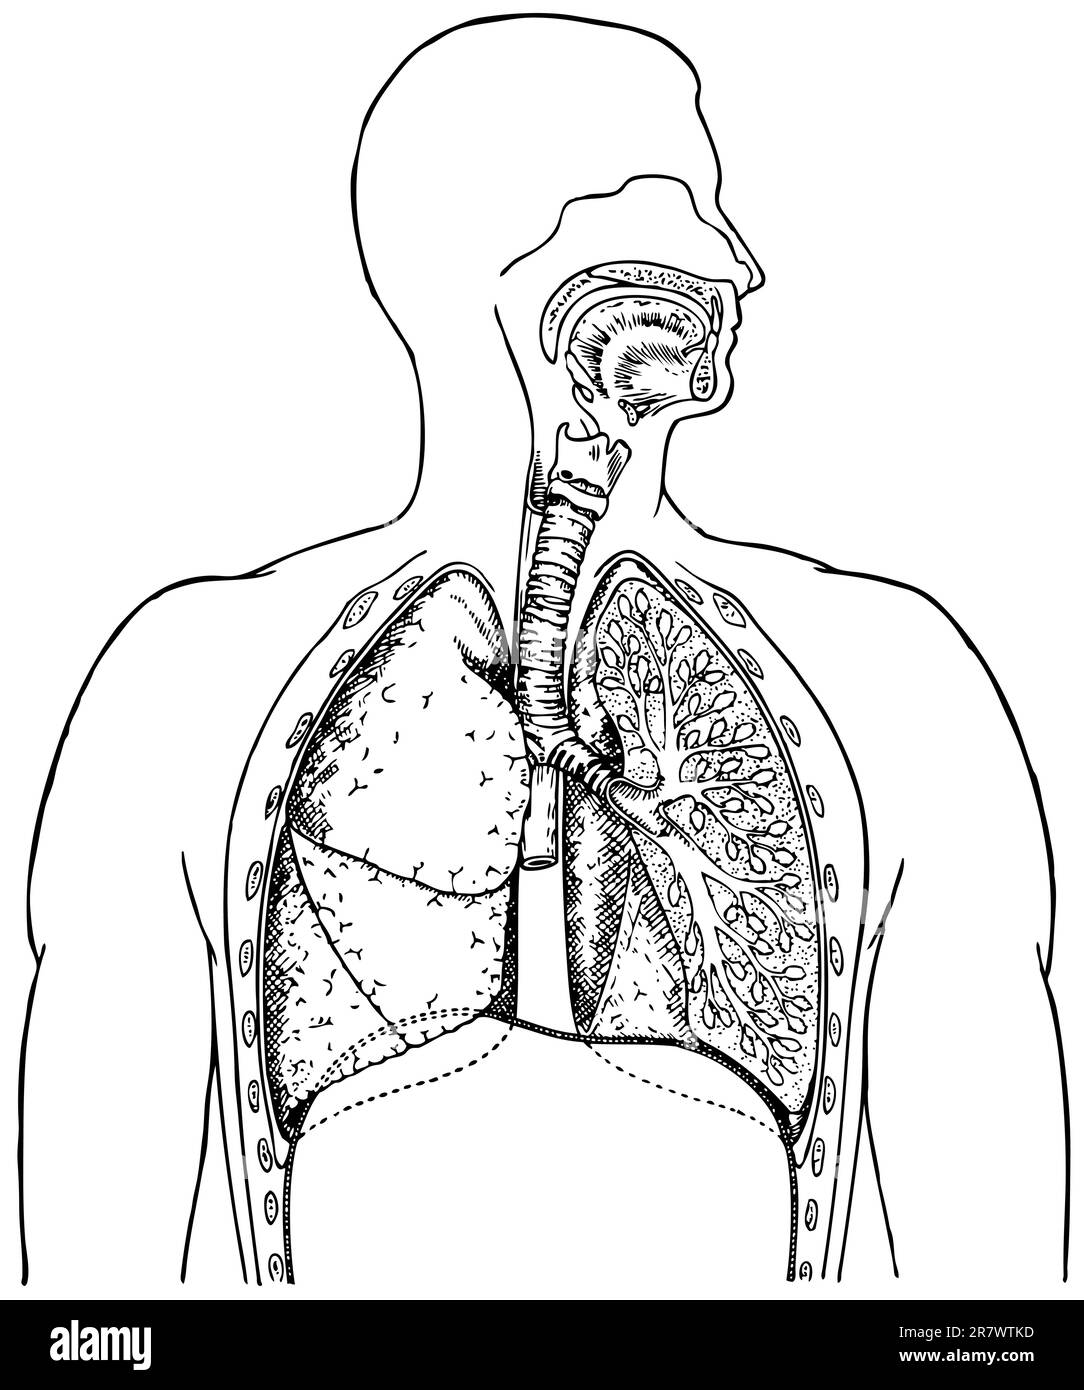

Système respiratoire humain sur fond blanc Illustration de Vecteurhttps://www.alamyimages.fr/image-license-details/?v=1https://www.alamyimages.fr/systeme-respiratoire-humain-sur-fond-blanc-image555602529.html

Système respiratoire humain sur fond blanc Illustration de Vecteurhttps://www.alamyimages.fr/image-license-details/?v=1https://www.alamyimages.fr/systeme-respiratoire-humain-sur-fond-blanc-image555602529.htmlRF2R7WTKD–Système respiratoire humain sur fond blanc